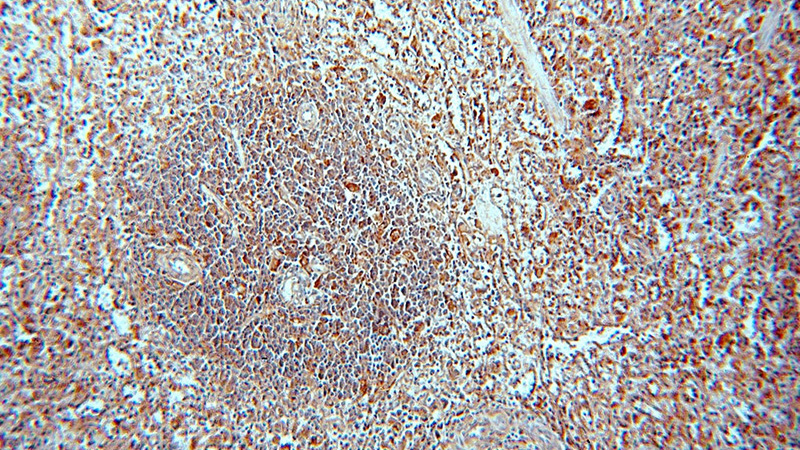

Immunohistochemical of paraffin-embedded human spleen using Catalog No:113487(PAFAH1B3 antibody) at dilution of 1:50 (under 10x lens)

Immunohistochemical of paraffin-embedded human spleen using Catalog No:113487(PAFAH1B3 antibody) at dilution of 1:50 (under 40x lens)